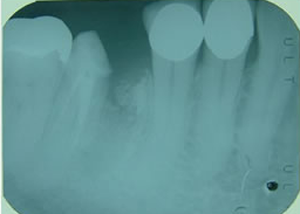

症例3 57歳 男性

2008 10/18 更新

矢島歯科院長

治療経過こちら

右下

第一第臼歯近心根破折

(大臼歯は歯根が二つに分かれている)

1.H18.4.12

抜歯後

(某歯科医院にて手前の歯根のみ抜歯)

2.インプラントする前

(抜歯後4ヶ月弱)

3.H18.8.22

抜いたところにインプラント埋入

(助手に鏡を持ってもらい、それを見ながら埋入)

4.紺屋の白袴中

5.インプラントに支台を入れたところ

6.上部の冠をつけたところ

7.大臼歯を2個の歯に分けて入れました。

良好に使用中